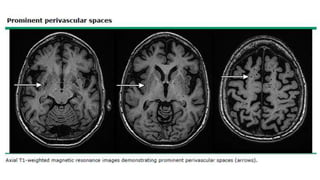

• Pequeñas áreas

redondeadas (<10 mm) de

pérdida de señal

(hipointensidad) áreas

depósito hemosiderina.

Microsangrados:

• Hipointensidad lineal a lo

largo de superficie cortical.

• A lo largo circunvolución

supratentorial simple o

múltiple→ gral/ Sg AAC,

otras causas hemorragia

superficial (Malform

vasculares o trombosis

venosa cortical).

Siderosis

superficial:

• Gral/ no se informan en

práctica radiológica de

rutina. Se vuelven más

visibles en pctes con enf

cerebrales de pequeños

vasos.

• Atrofia: atrofia cerebral

acelerada.

Espacios

perivasculares:

Eric B Larson. Evaluation of cognitive impairment and dementia. ©2020 UpToDate, review April 2020.